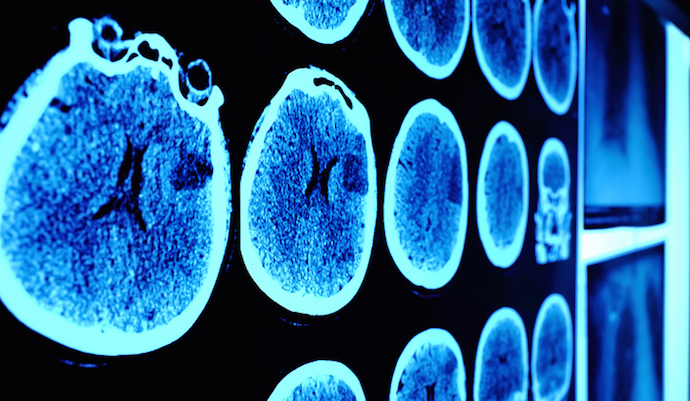

سرطان همچنین ممکن است از طریق جریان خون به نقاط دور بدن مانند استخوان ، کبد ، ریه یا مغز منتقل شود.حتی اگر سرطان گسترش یابد، هنوز نام آن مریوط به ناحیه ای است که در آن شروع شده است. به عنوان مثال، اگر سرطان سینه به ریه ها سرایت کند، سرطان پستان متاستاتیک نامیده می شود، نه سرطان ریه.